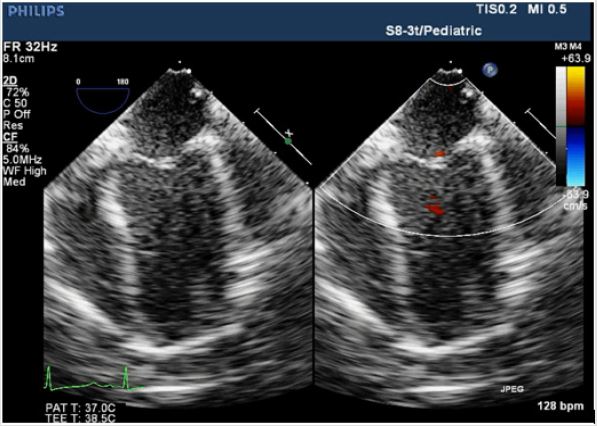

With standard anesthetic induction and tracheal intubation, evaluation by TEE (S8-3t/Pediatric, PHILIPS) was performed not only to reconfirm the location and degree of SAS (Figure 2A), but also for providing evidence to choose appropriate size/diameter of aortic cannulation. Median sternotomy was proceeded to expose the heart, CPB was achieved via the ascending aorta upper the narrowest location and the right atrium, and the surgical aortic and pulmonic stenosis correction went well. Unfortunately, the invasive blood pressure (IBP) was difficult to maintain without CPB’s support after heart resuscitation. Meanwhile, TEE showed the right heart functioned well. Contrarily, the left ventricular was enlarged coupled with shrinkage force was extremely weaken and mitral regurgitation (Figures 2B & 2C). Minutes later, ventricular fibrillation occurred, and defibrillation was proceeded. CPB ran again, reluctantly and repeatedly. Surgeons advised anesthetists to pump norepinephrine (2ug/kg/min) intravenously to increase the cardiac after-load, unfortunately, this process leaded to much more difficulty in removing CPB.

Figure 2A: Intraoperative TEE; Four-chamber view showed symmetry of ventricular size and the whole cardiac contractility was almost normal before surgery proceeded.

Figure 2B: Intraoperative TEE. Compared with preoperative values, TEE images showed the shrinkage force of left ventricular was weaken, coupled with mitral regurgitation. The left atrial and left ventricular was dilated seriously and the pressures measured by surgeons were 20mmHg and 12mmHg, respectively.

Figure 2C: Intraoperative TEE. The left ventricular myocardial contractility taken a turn for better, the shape of left ventricular was almost reached the normal level and mitral regurgitation alleviated after the surgeons reconstructed the left coronary cusp.

According to TEE real-time images, combined with the “linear graph of angiocarpy” (a patent work from Hai-bo Song, patent number: 2015-L-00247942) (Figure 3), surgeons were suggested to check the cardiac apex’s appearance, even coronary cusps and coronary arteries if the occasion should arise. The cardiac apex was wan without contractility! After open the aortic incision upper the non-coronary cusp decidedly for exploration, surgeons saw the coronary cusps were all abnormal deep and the non-coronary cusp after ascending aorta was broadened was relatively too large to compressed the left coronary cusp in ventricular diastole phase, which resulted in insufficient blood supplied to the left coronary artery generated dyspraxia and dilation of left ventricular related to mitral regurgitation(Figure 2B). Accordingly, surgeons broadened the left coronary cusp carefully using autologous pericardium. Finally, the left ventricular myocardial contractility taken a turn for better, the shape of left ventricular was almost reached the normal level preoperative and mitral regurgitation alleviated (Figure 2C). The whole CPB time was 286 minutes, ultrafiltration technology was used to wipe out inflammation factors. The baby patient suffered hemorrhage and pericardial tamponade in intensive care unit. After supportive treatments were given, the baby had an ideal recovery and discharged fifteen days later. Regular follow-up showed no abnormality.